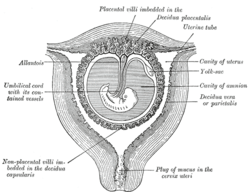

Sectional plan of the gravid human uterus in the third and fourth months of pregnancy | |

In mammals (excluding monotremes), the allantois is part of and forms an axis for the development of the umbilical cord.

- The human allantois is an endodermal evagination of the developing hindgut which becomes surrounded by the mesodermal connecting stalk known as the body-stalk. The body-stalk forms the umbilical vasculature. In other words, the allantois is a caudal diverticulum (out-pouching) of the yolk-sac. It is externally continuous with the proctodeum and internally continuous with the cloaca. The embryonic allantois becomes the fetal urachus which connects the fetal bladder (developed from cloaca) to the yolk sac. The urachus removes nitrogenous waste from the fetal bladder.[3] The allantois is vestigial and may regress, yet the homologous blood vessels persist as the umbilical arteries and veins connecting the embryo with the placenta.[4]